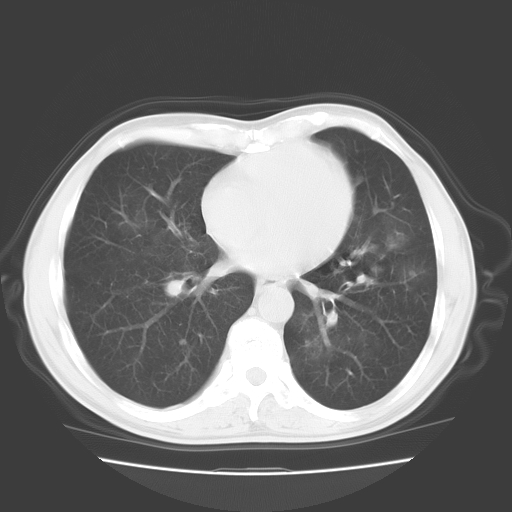

以下是引用随光逐影在2008-11-20 23:02:00的发言:[br]1)考虑左肺上叶周围型肺癌可能性大。2)两肺散在性肺泡积血。[br][br][本贴已被 随光逐影 于 2008-11-20 23:09:31 修改过]

以下是引用drzhang8888在2008-11-20 22:20:00的发言:[br]密集的短毛刺,血管集束,胸膜凹陷,周边型肺癌可能性大,另双肺多发磨玻璃影,考虑感染

以下是引用流浪星在2008-11-20 22:28:00的发言:[br]左肺上叶近外围区见一类圆形结节影,毛刺征、胸膜尾征阳性,临近肺组织见多发渗出灶。考虑1,炎症性病变。 2.周围性肺癌。建议抗炎治疗后复查。